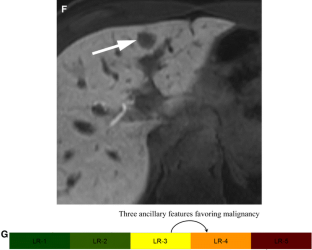

LI-RADS® algorithm: CT and MRI

The Liver Imaging Reporting and Data System (LI-RADS®) is an imaging-based diagnostic system applicable in patients at high risk of hepatocellular carcinoma (HCC). In LI-RADS, each liver observation is assigned a category that reflects probability of benignity, HCC, or other malignancy. Familiarity with the LI-RADS diagnostic algorithm is necessary to appropriately implement LI-RADS in clinical practice. This review discusses steps necessary for application of the LI-RADS algorithm and provides examples illustrating each step.